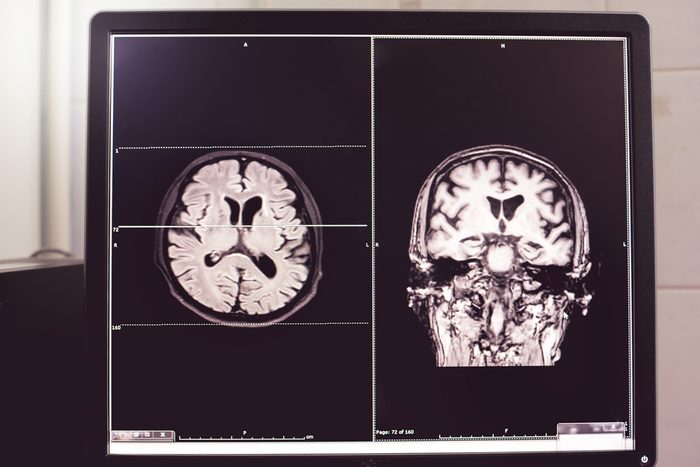

mri brain scan

Atthapon Raksthaput/Shutterstock

Alzheimer’s can only be treated after a diagnosis

Doctors used to believe that you couldn’t do anything about Alzheimer’s until symptoms appeared. “In the past few years, there’s been a shift in the thinking for many of us who study dementia. We’ve come to the conclusion that the best time to treat Alzheimer’s disease is before the earliest symptoms surface,” says Dr. Kosik. “This shift has been brought on by new technology that allows us to peer inside the human brain… We now know that the Alzheimer’s plaques begin to proliferate ten or even 20 years before the first Alzheimer’s symptoms become noticeable.” These are the early signs of Alzheimer’s that every adult should know.